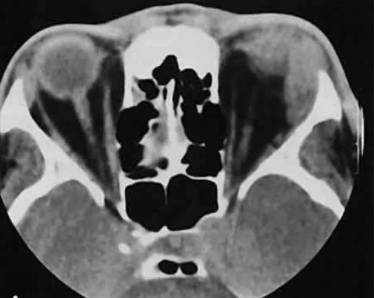

Диагностика:

• лабораторные исследования крови и тканей из ран;

• рентгенологическое исследование позвоночника;

• МРТ;

• КТ.